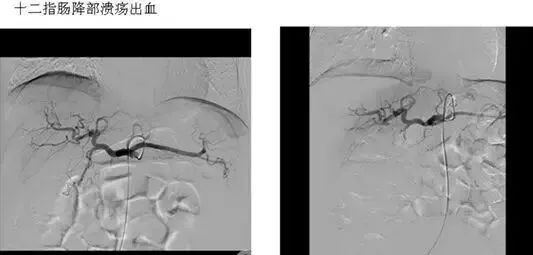

五、出血性疾病:鼻腔大出血、咯血、上消化道大出血、经皮肾镜术后出血、膀胱出血、产后出血等

(1)血管收缩治疗 经导管向有关动脉内滴注加压素,以控制胃肠道出血,例如食道胃静脉曲张出血、胃粘膜弥漫性出血及结肠憩室出血等等。

(5)应用栓塞术或血管加压素治疗胃肠道血管出血。